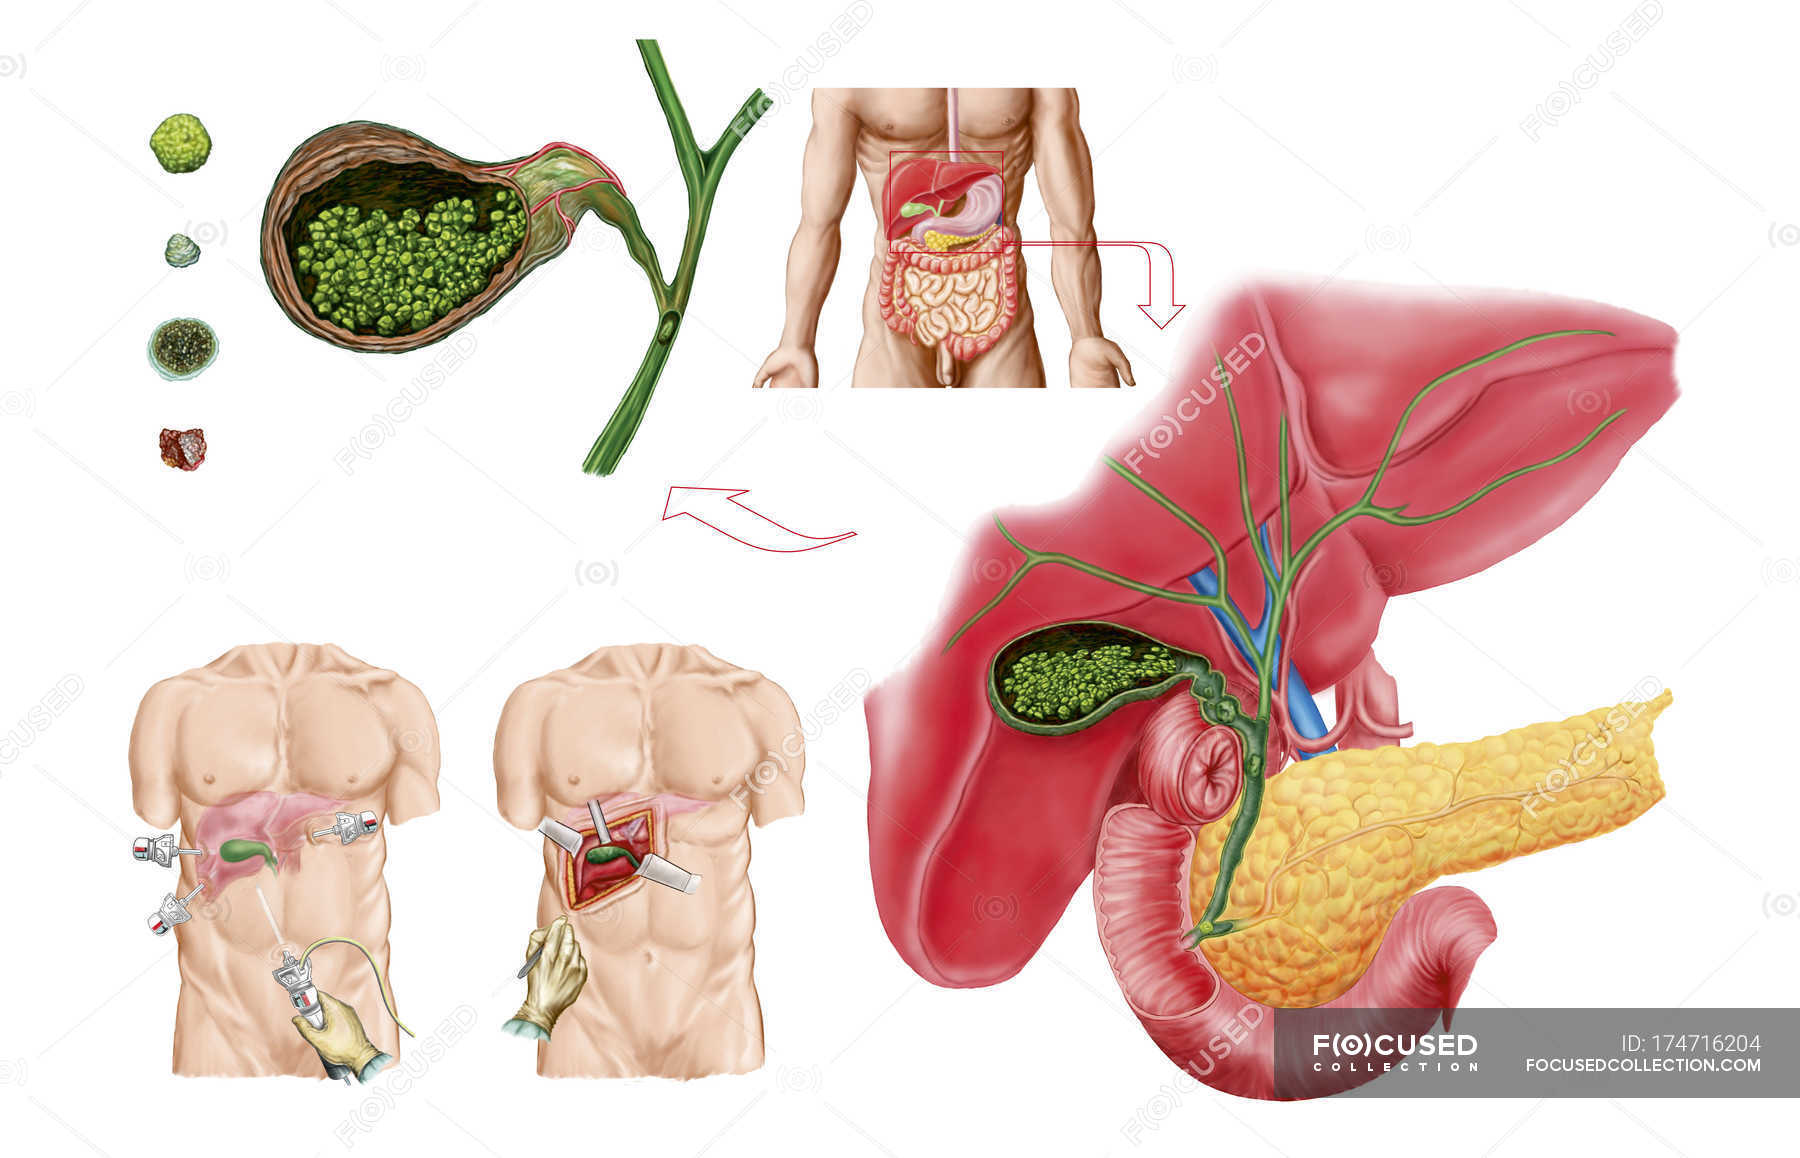

Анатомия и особенности Гартманова кармана желчного пузыря